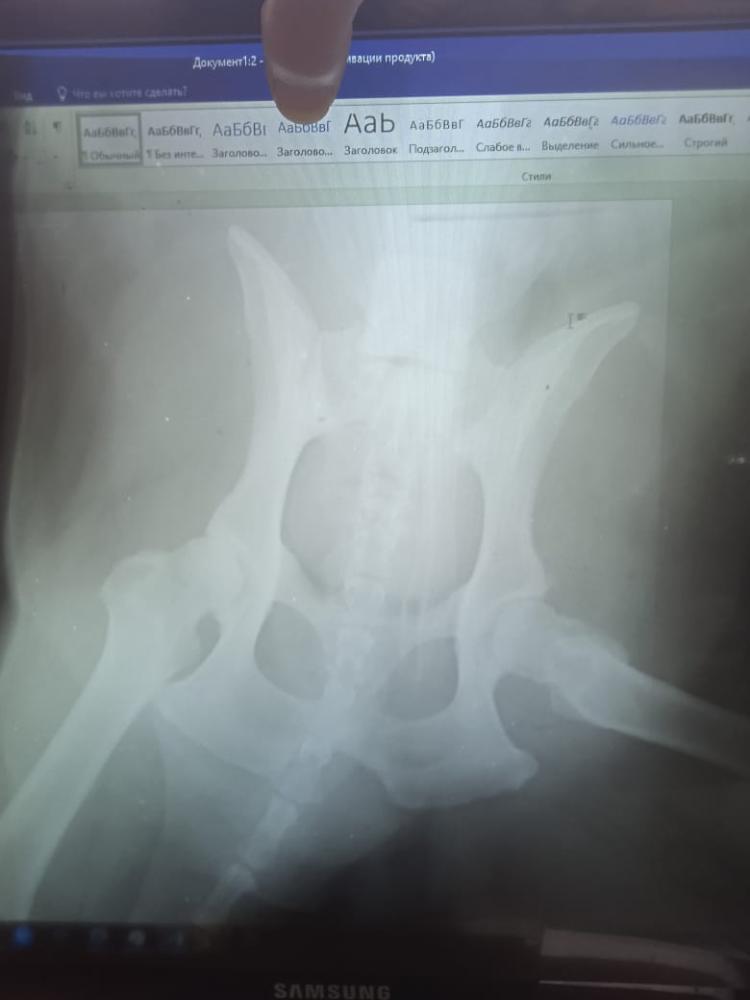

Собака голден ретривер, 13,5 лет

Диагноз по рентгену - спондилез L4-L5 поставлен в марте 22г собака стала тяжело вставать.

Сейчас состояние ухудшается, собака почти не может ходить, задние лапки выворачиваются в другую сторону, пытается ходить, но как на култышках, подушки не чувствует.

Вес ориентировочно 37-40 кг. ( он крупный, не толстый). Посоветуйте пожалуйста нам , что еще можно сделать, собака возрастная, крепкий еще, глазки веселые, а лапы не идут. Поддерживаем постоянно, в туалет ходит на улице, с этим пока все в порядке . Мрт боимся делать, так как наркоз, а собаке почти 14 лет